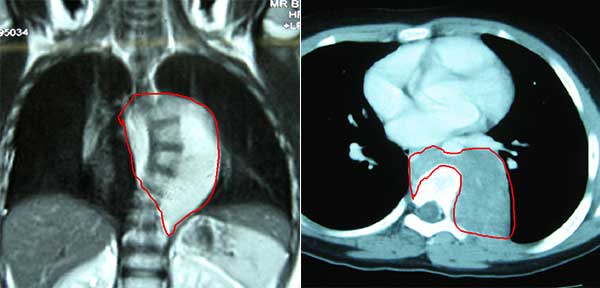

年仅8岁的嘉嘉无意间被父母发现脊柱侧弯畸形,经CT检查发现后纵隔长了一个大小约10cm×7.5cm的肿瘤,形状像个大萝卜,紧贴并包绕降主动脉、胸椎、椎间孔和后胸壁并跨过脊柱对侧,并且从降主动脉内分出多支肿瘤滋养血管。小孩子自己没什么感觉,倒是吓坏了嘉嘉父母。辗转就诊省内多家知名大医院,均因手术风险大,担心肿瘤如果侵犯降主动脉无法彻底切除或导致致命的大出血而不能收入院手术治疗。嘉嘉父母通过熟人、朋友和网络四处查询打听,最终了解到我院胸外科是国家临床重点专科,在治疗胸腔中肿瘤有丰富经验时,抱者一丝希望带着嘉嘉来到我院胸外科就诊。该科主任陈刚接诊患儿后,认真阅片、详细询问检查患儿后告知其父母,如果要彻底切除肿瘤,手术难度非常大、风险很高,但不切除肿瘤嘉嘉的病情会越来越重,而且脊柱侧弯也会继续加重。

红色区域的巨大肿瘤紧贴并包绕胸椎